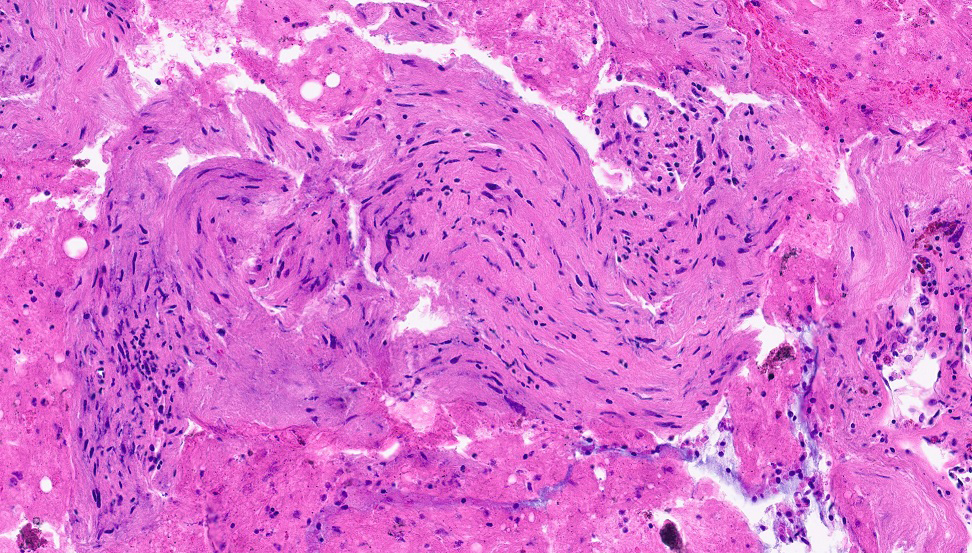

Figure 5: Cell block, Hematoxylin and Eosin (H&E) stain

The FNA aspirate smears (Figure 1 to 4) show clusters of spindle shaped cells arranged in short fascicles with pale eosinophilic cytoplasm, and slender wavy or buckled nuclei. No significant nuclear atypia, mitotic activity or necrosis was identified. Variable amount of collagenous material separates these spindle cells. The cell block (Figure 5) shows cohesive tissue fragments, with fibrillary stroma and focal palisading of the spindle, wavy, or fish-hook–like nuclei with pointed ends. The spindle cells show fine chromatin, smooth and regular nuclear membranes, and inconspicuous nucleoli and bipolar spindle cytoplasm. Immunocytochemical stain performed on the cell block reveals that spindle cells are positive for S-100 (Figure 6). The cells also showed nuclear positivity for SOX-10, while they were negative for cytokeratin AE1/3 and CAM5.2, CD68, CD34, CD117, DOG1, ERG, MelanA, and HMB45 (Not shown).

The conventional schwannomas are spindle cell neoplasms with alternating Antoni A (compact) and Antoni B (hypocellular) patterns. Verocay bodies, characterized by nuclear palisading, may be present. The spindle cells have pale eosinophilic cytoplasm and ovoid or tapered nuclei. Some tumors exhibit cytoplasmic nuclear pseudoinclusions, mild pleomorphism, and mitotic activity. Ancient schwannomas show scattered atypical or bizarre nuclei with dark, smudgy chromatin, indicating degenerative changes.